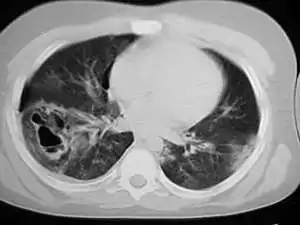

| سی تی اسکن قفسه سینه، کوفتگیهای ریوی، پنوموتوراکس و کیستهای کاذب را نشان میدهد | |